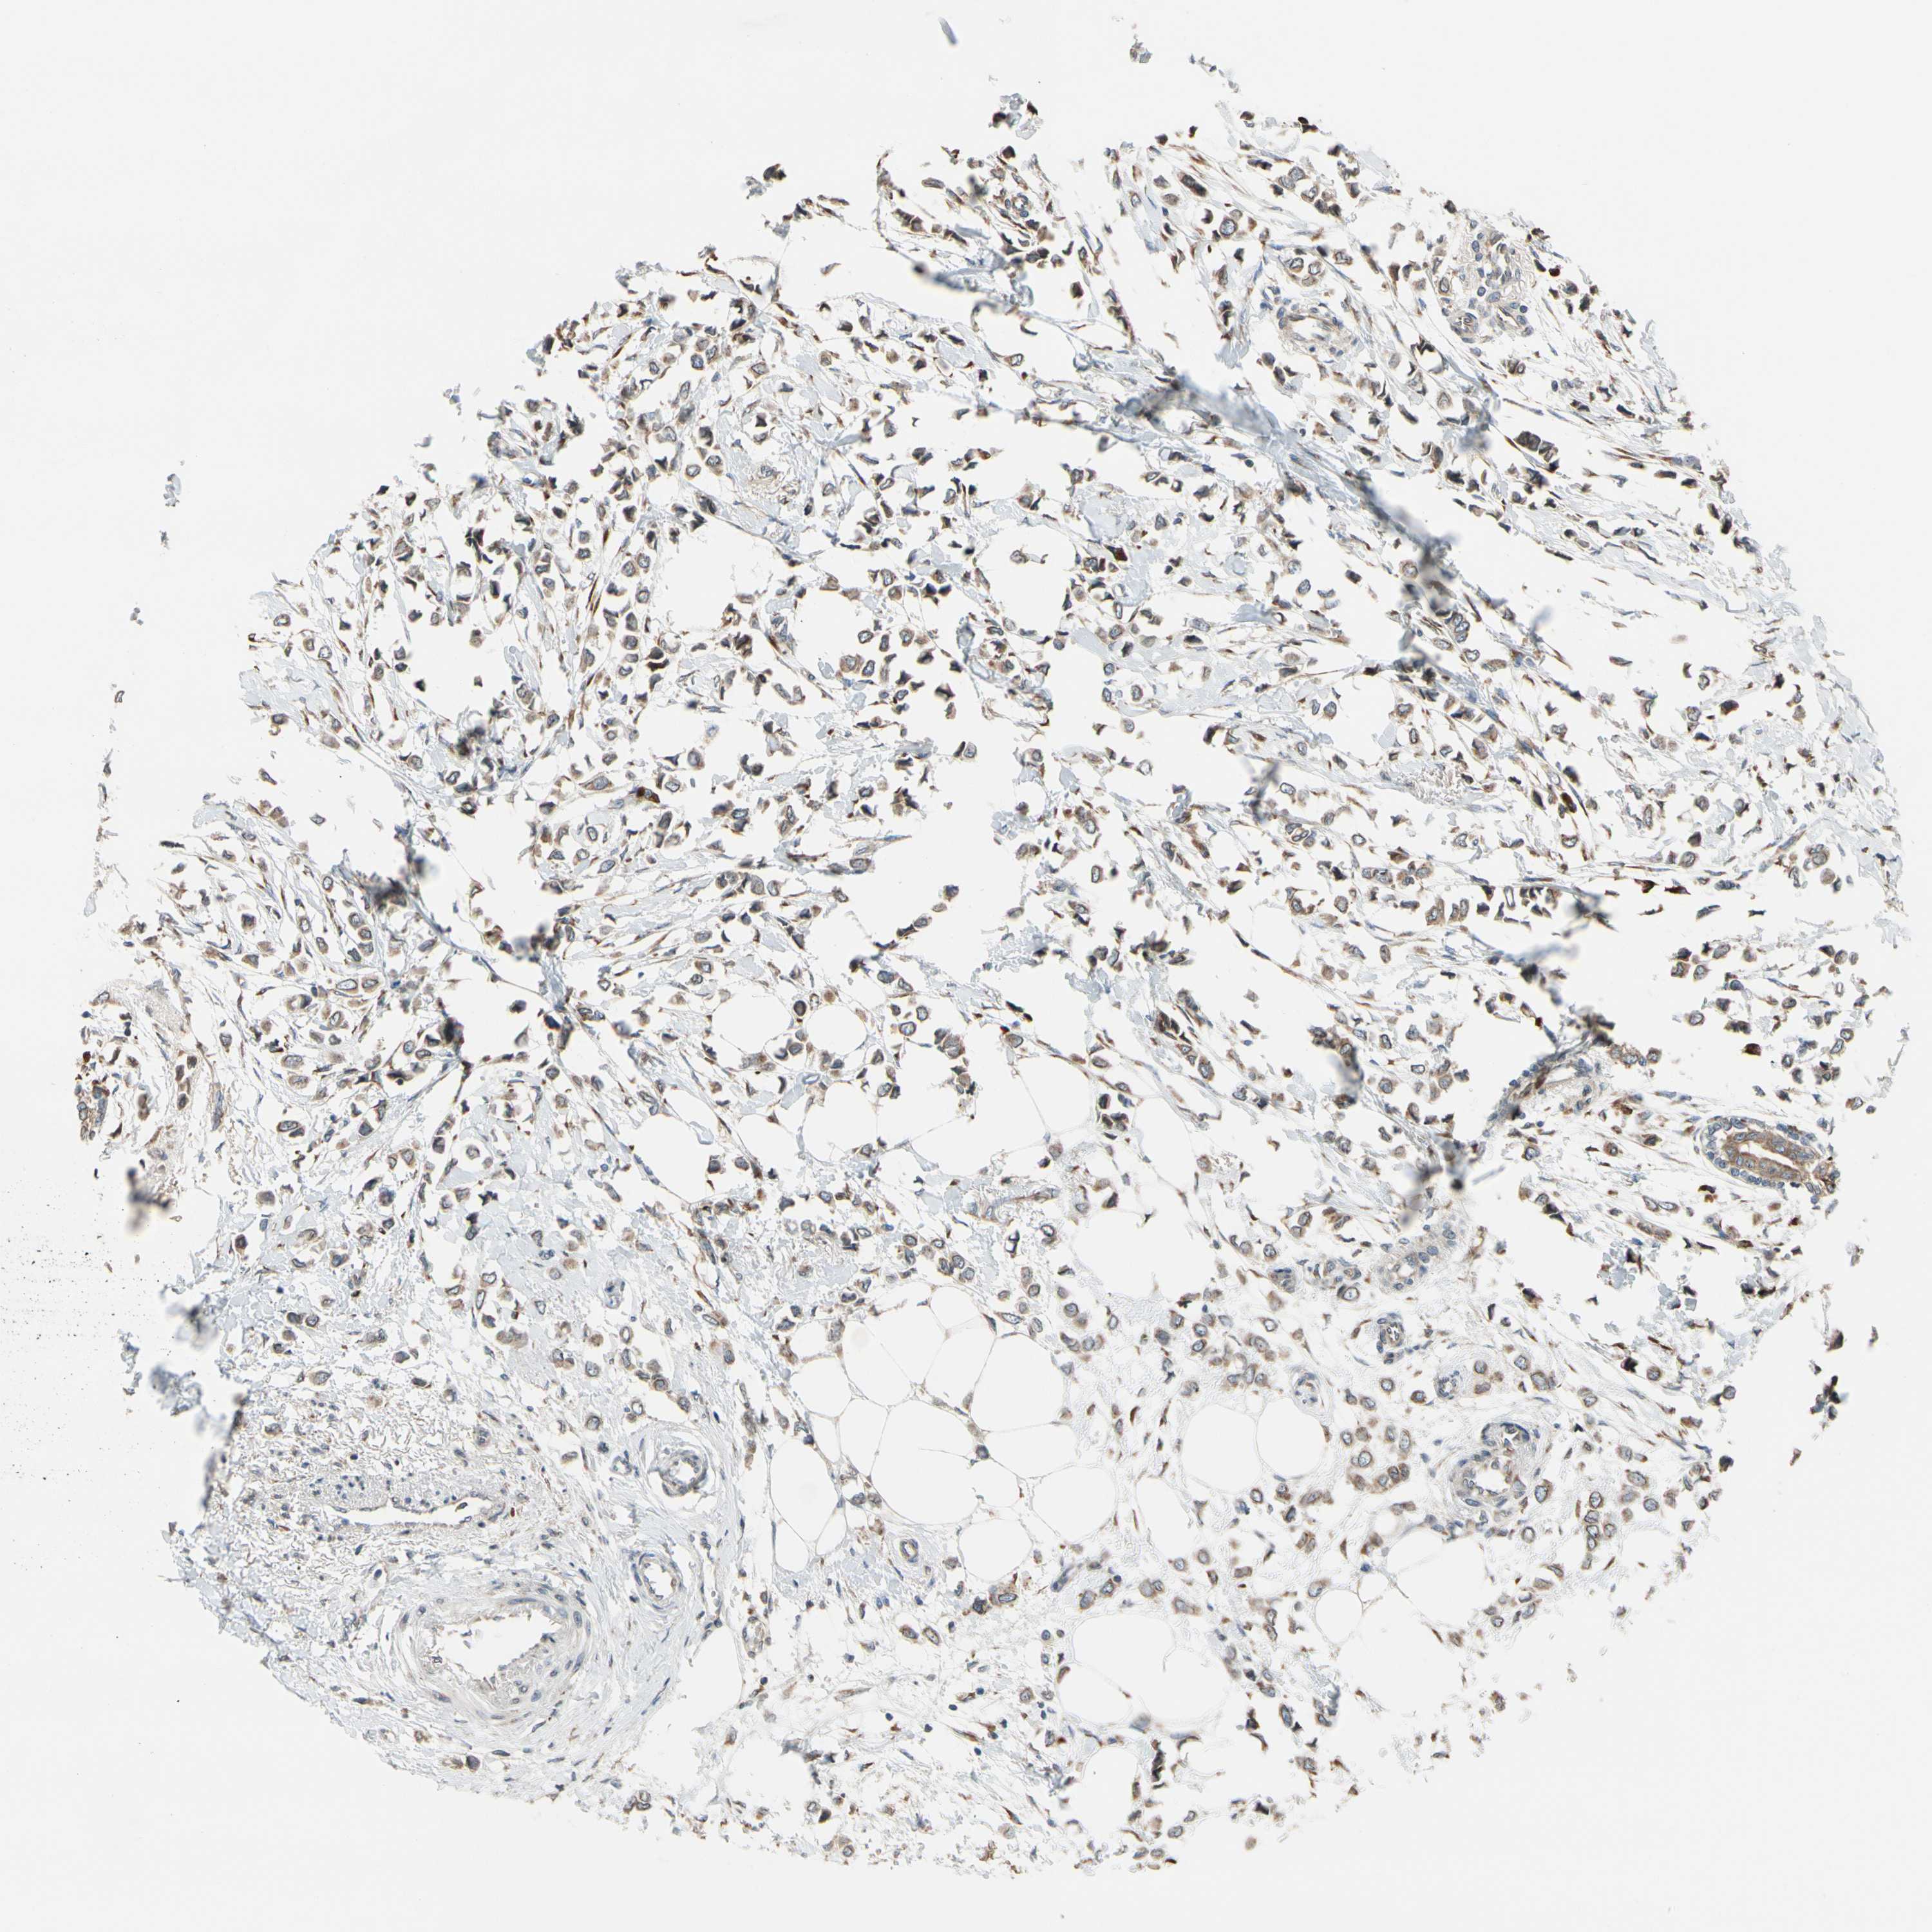

CANCER BREAST CANCER Show tissue menu

BRCA TCGA BRCA VALIDATION PROTEIN EXPRESSION

Breast cancer

Human cancer